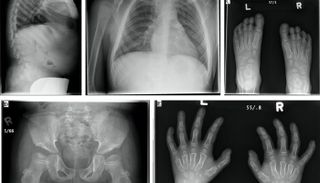

ويؤدي هذا النقص إلى تراكم المواد السكرية المعقدة في أنسجة الجسم، مسببا تشوهات هيكلية شديدة منذ الطفولة المبكرة ومشكلات متعددة في القلب والعينين والمفاصل، بينما يبقى الإدراك العقلي غالبا سليما.

الدراسة التي حصلت العين الإخبارية على نسخة منها، وتنشرها دورية "مولكيولار جينيتكس آند ميتابوليزم ريبورتس" هذا الشهر، راقبت 33 طفلا من 26 عائلة عراقية مختلفة، وسجلت أن أكثر من 90% منهم ينحدرون من أسر متزوجة بين الأقارب، ما يعكس التحديات الوراثية في المجتمع العراقي. وأكدت النتائج وجود تأخر كبير في النمو، تشوهات هيكلية عامة، عتامة القرنية، أمراض صمامات القلب، وفقدان السمع لدى أغلب الأطفال.

وأشارت الدراسة إلى أن الأعراض تظهر عادة في سن مبكرة جداً، إلا أن التشخيص عالبا ما يتأخر لسنوات، مما يعيق التدخل العلاجي المبكر. وأكد الباحثون أن الفحص الجيني المبكر، وإنشاء سجلات وطنية للمرضى، والمتابعة متعددة التخصصات، ضرورية للحد من المضاعفات وتحسين جودة حياة المرضى.